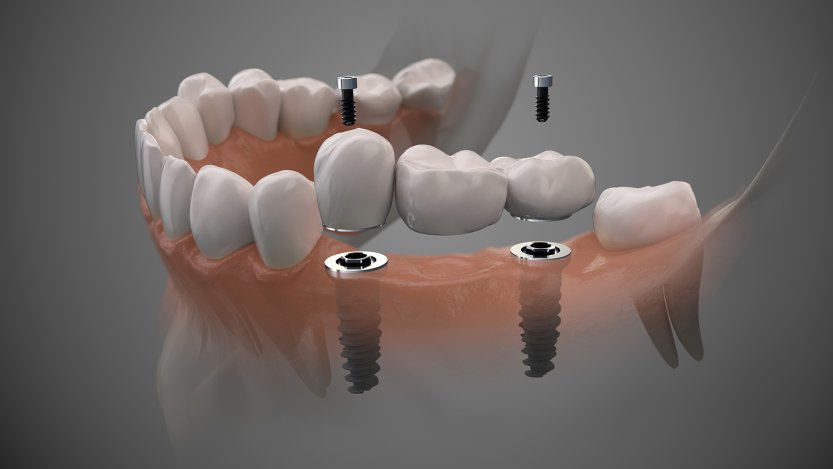

A fogimplantátum célja, hogy helyettesítse egy vagy több kihúzott fog funkcióját. Úgy kell elképzelni, hogy a beültetett fogimplantátum úgy működik, mint egy foggyökér, tehát a gyógyulását követően ellátható különböző fogpótlásokkal. Teljes fogatlanság esetén több fogimplantátumot szükséges beültetni, ezek száma 4-6-8, esetleg 10 db állcsontonként. Ezekre a fogimplantátumkra készül el és rögzül a fogpótlás, lehetőség szerint csavarozható megoldással. Az implantációs fogpótlások rendkívüli precizitással kell készüljenek, erre a digitális (CAD-CAM) gyártás technológia a legalkalmasabb.

A fogimplantátumra készített pótlások anyaga lehet fémtartalmú is, de rendelőnk a biokompatibilitás és pontosság miatt szinte kizárólag cirkónium alapú megoldásokkal áll a páciensek rendelkezésére. A koronák, hidak átmenő csavarral rögzülnek a fogimplantátum belsejében kialakított “fészekbe”, így szükség esetén károsítás nélkül eltávolíthatóak, tisztíthatóak, javíthatóak.

Amennyiben csak részlegesen hiányoznak fogak és azokat fogimplantátumokkal helyettesítettük, akkor rövidebb hidak készülnek, lehetőség szerint szintén csavarrögzítéssel. Előfordul, hogy csupán egyetlen fog hiányzik és annak helyére kerül beültetésre fogimplantátum. Ha ez a hiányzó fog a mosolyzónában helyezkedik el, akkor kiemelt és kritikus fontosságú a fogimplantátumra készülő fogpótlás természetes megjelenése.